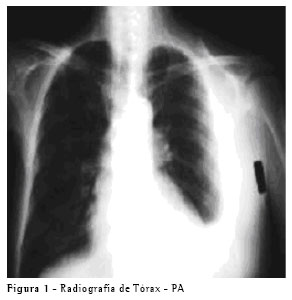

RELATO DO CASO Paciente do sexo masculino, de 65 anos, procurou o Ambulatório de Doenças Pleurais do Hospital das Clínicas da Faculdade de Medicina da Universidade de São Paulo por orientação de seu cardiologista, com história de dispnéia e perda de peso. O paciente apresentava no seu histórico médico o diagnóstico de insuficiência cardíaca, e encontrava-se em vigência de tratamento adequado. Na propedêutica foram encontrados frêmito toracovocal e murmúrio vesicular diminuídos à esquerda e ausência de sinais de descompensação cardíaca. A radiografia de tórax mostrava um derrame pleural moderado à esquerda, sem alterações no mediastino (Figura 1). O paciente foi submetido a toracocentese, para alívio dos sintomas e com finalidade diagnóstica.